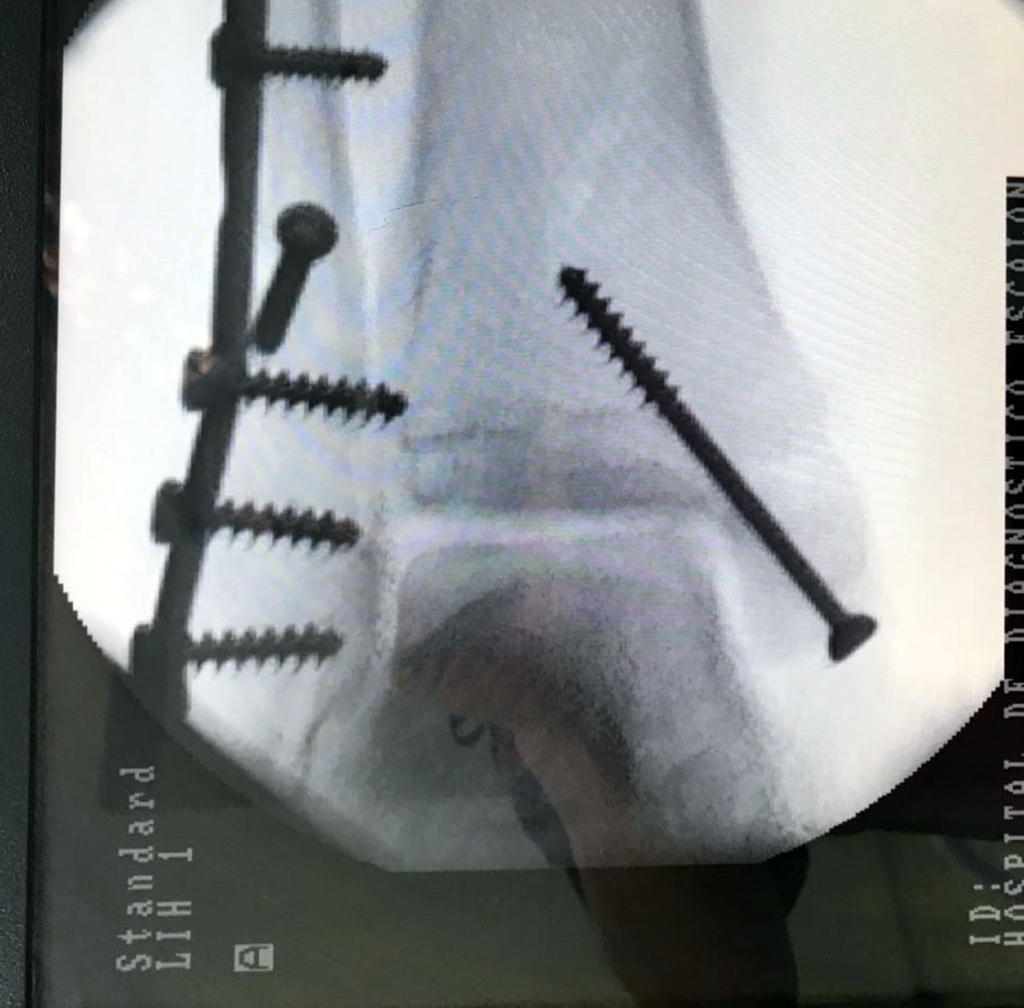

Cuando se necesita cirugía, es probable que esta implique el uso de clavijas de metal, tornillos o placas para sostener los huesos en su lugar mientras la fractura se consolida. Los elementos de soporte pueden ser temporales o permanentes.

Algunas fracturas de tobillo pueden requerir cirugía si:

- El médico cree que sus huesos probablemente no sanen apropiadamente sin cirugía.

- El médico considera que la cirugía puede permitirle una recuperación más rápida y confiable.